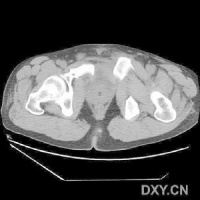

CT检查对骨盆骨折虽不属常规但它可在多个平面上清晰显示骶髂关节及其周围骨折或髋臼骨折的移位情况,因此凡涉及后环和髋臼的骨折应行CT检查骨盆三维重建CT或螺旋CT检查更能从整体显示骨盆损伤后的全貌,对指导骨折治疗颇有助益但应铭记对血流动力学鵻不稳定和多发伤患者,后前位全骨盆X线片是最基本和最重要鵻的放射学检查不要在拍摄特殊X线片上花费时间,更为重要的是尽快复苏。